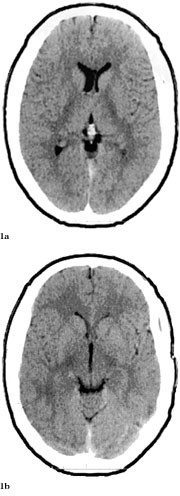

Pasienten ble overflyttet til Namdal Sykehus 6.6. Han var somnolent, desorientert og gav stereotype svar. Han hadde ingen fokale utfall. På mistanke om herpes simplex-encefalitt ble det iverksatt behandling med aciklovir 3 ⋅ 750 mg intravenøst, i tillegg fenytoin 2 ⋅ 250 mg intravenøst mot symptomatiske epileptiske anfall. Dagen etter ble pasienten soporøs. EEG var preget av en generalisert langsom aktivitet, delvis i form av bilateral synkron, rytmisk deltaaktivitet (frontal intermittent rhythmic delta acitvity, FIRDA). CT viste symmetriske forandringer i basalgangliene og basale deler av cerebrum som var ødematøs (fig 2a, 2b). En ny spinalvæskeprøve, tatt 8.6., viste 17 celler. En CT fra 9.6. viste progredierende forandringer (fig 3).

Dessverre hadde vi ingen mulighet til å få utført MR og obduksjon. Likevel er en akutt demyeliniserende encefalomyelitt mindre sannsynlig på grunn av at sykdomsutviklingen ikke kom helt akutt, men var gradvis innsettende i løpet av ti dager. Dessuten hadde man ikke fokale eller multifokale motoriske eller sensible utfall (10, 13). CT-funn viste progredierende, symmetriske forandringer som gav hypodensitet først i basalganglier og senere generelt, men hele tiden mest i basale deler av storehjernen og i de limbiske strukturer (fig 1 – 3). Retrospektivt aner man allerede ved første CT-undersøkelse (fig 1b) små hypodense områder ut for 3. ventrikkel på hver side lavt i basalgangliene. Disse funnene tyder heller på en atypisk encefalitt enn på en akutt demyeliniserende encefalomyelitt og korresponderer med de kliniske funn av hukommelsesproblemer og personlighetsforandringer. Pasienten fikk terminalt sentral respirasjonsstans, noe som kan tyde på hjernestammeaffeksjon.

Sammenfattende hadde begge pasienter en sammenliknbar utvikling av de cerebrale symptomene: Nedsatt hukommelse og orientering, personlighetsforandringer, hjernestammesymptomer og generaliserte tonisk-kloniske anfall, men ingen fokale motoriske eller sensible utfall. Bildediagnostikken viste lesjoner i basalgangliene, spesielt i nucleus caudatus og limbiske strukturer, især i hippocampusområdet.